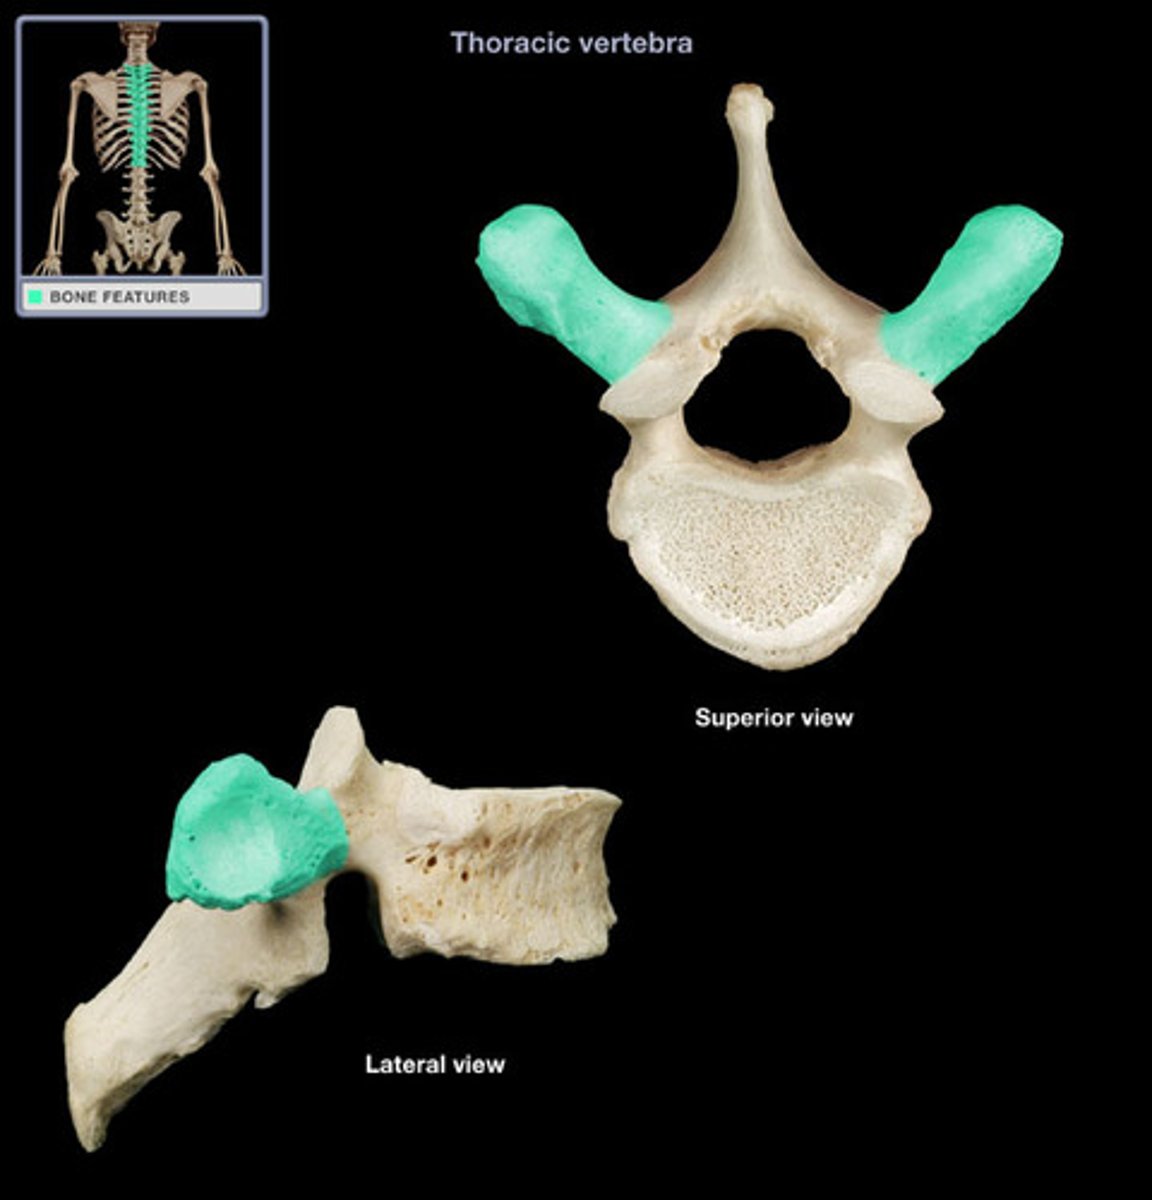

transverse process

What joint do the superior and inferior articulating processes form?

zygapophyseal joint

What is the unique characteristic of the thoracic spine?

facets for rib articulation

The THORACIC zygapophyseal joints are ONLY demonstrated on what view?

70 degree oblique